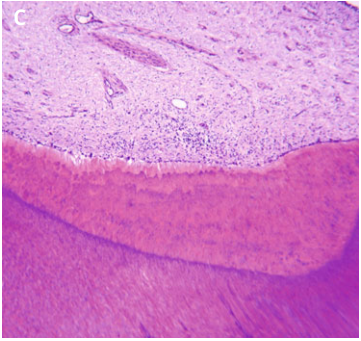

pulpitis reversible

1.png